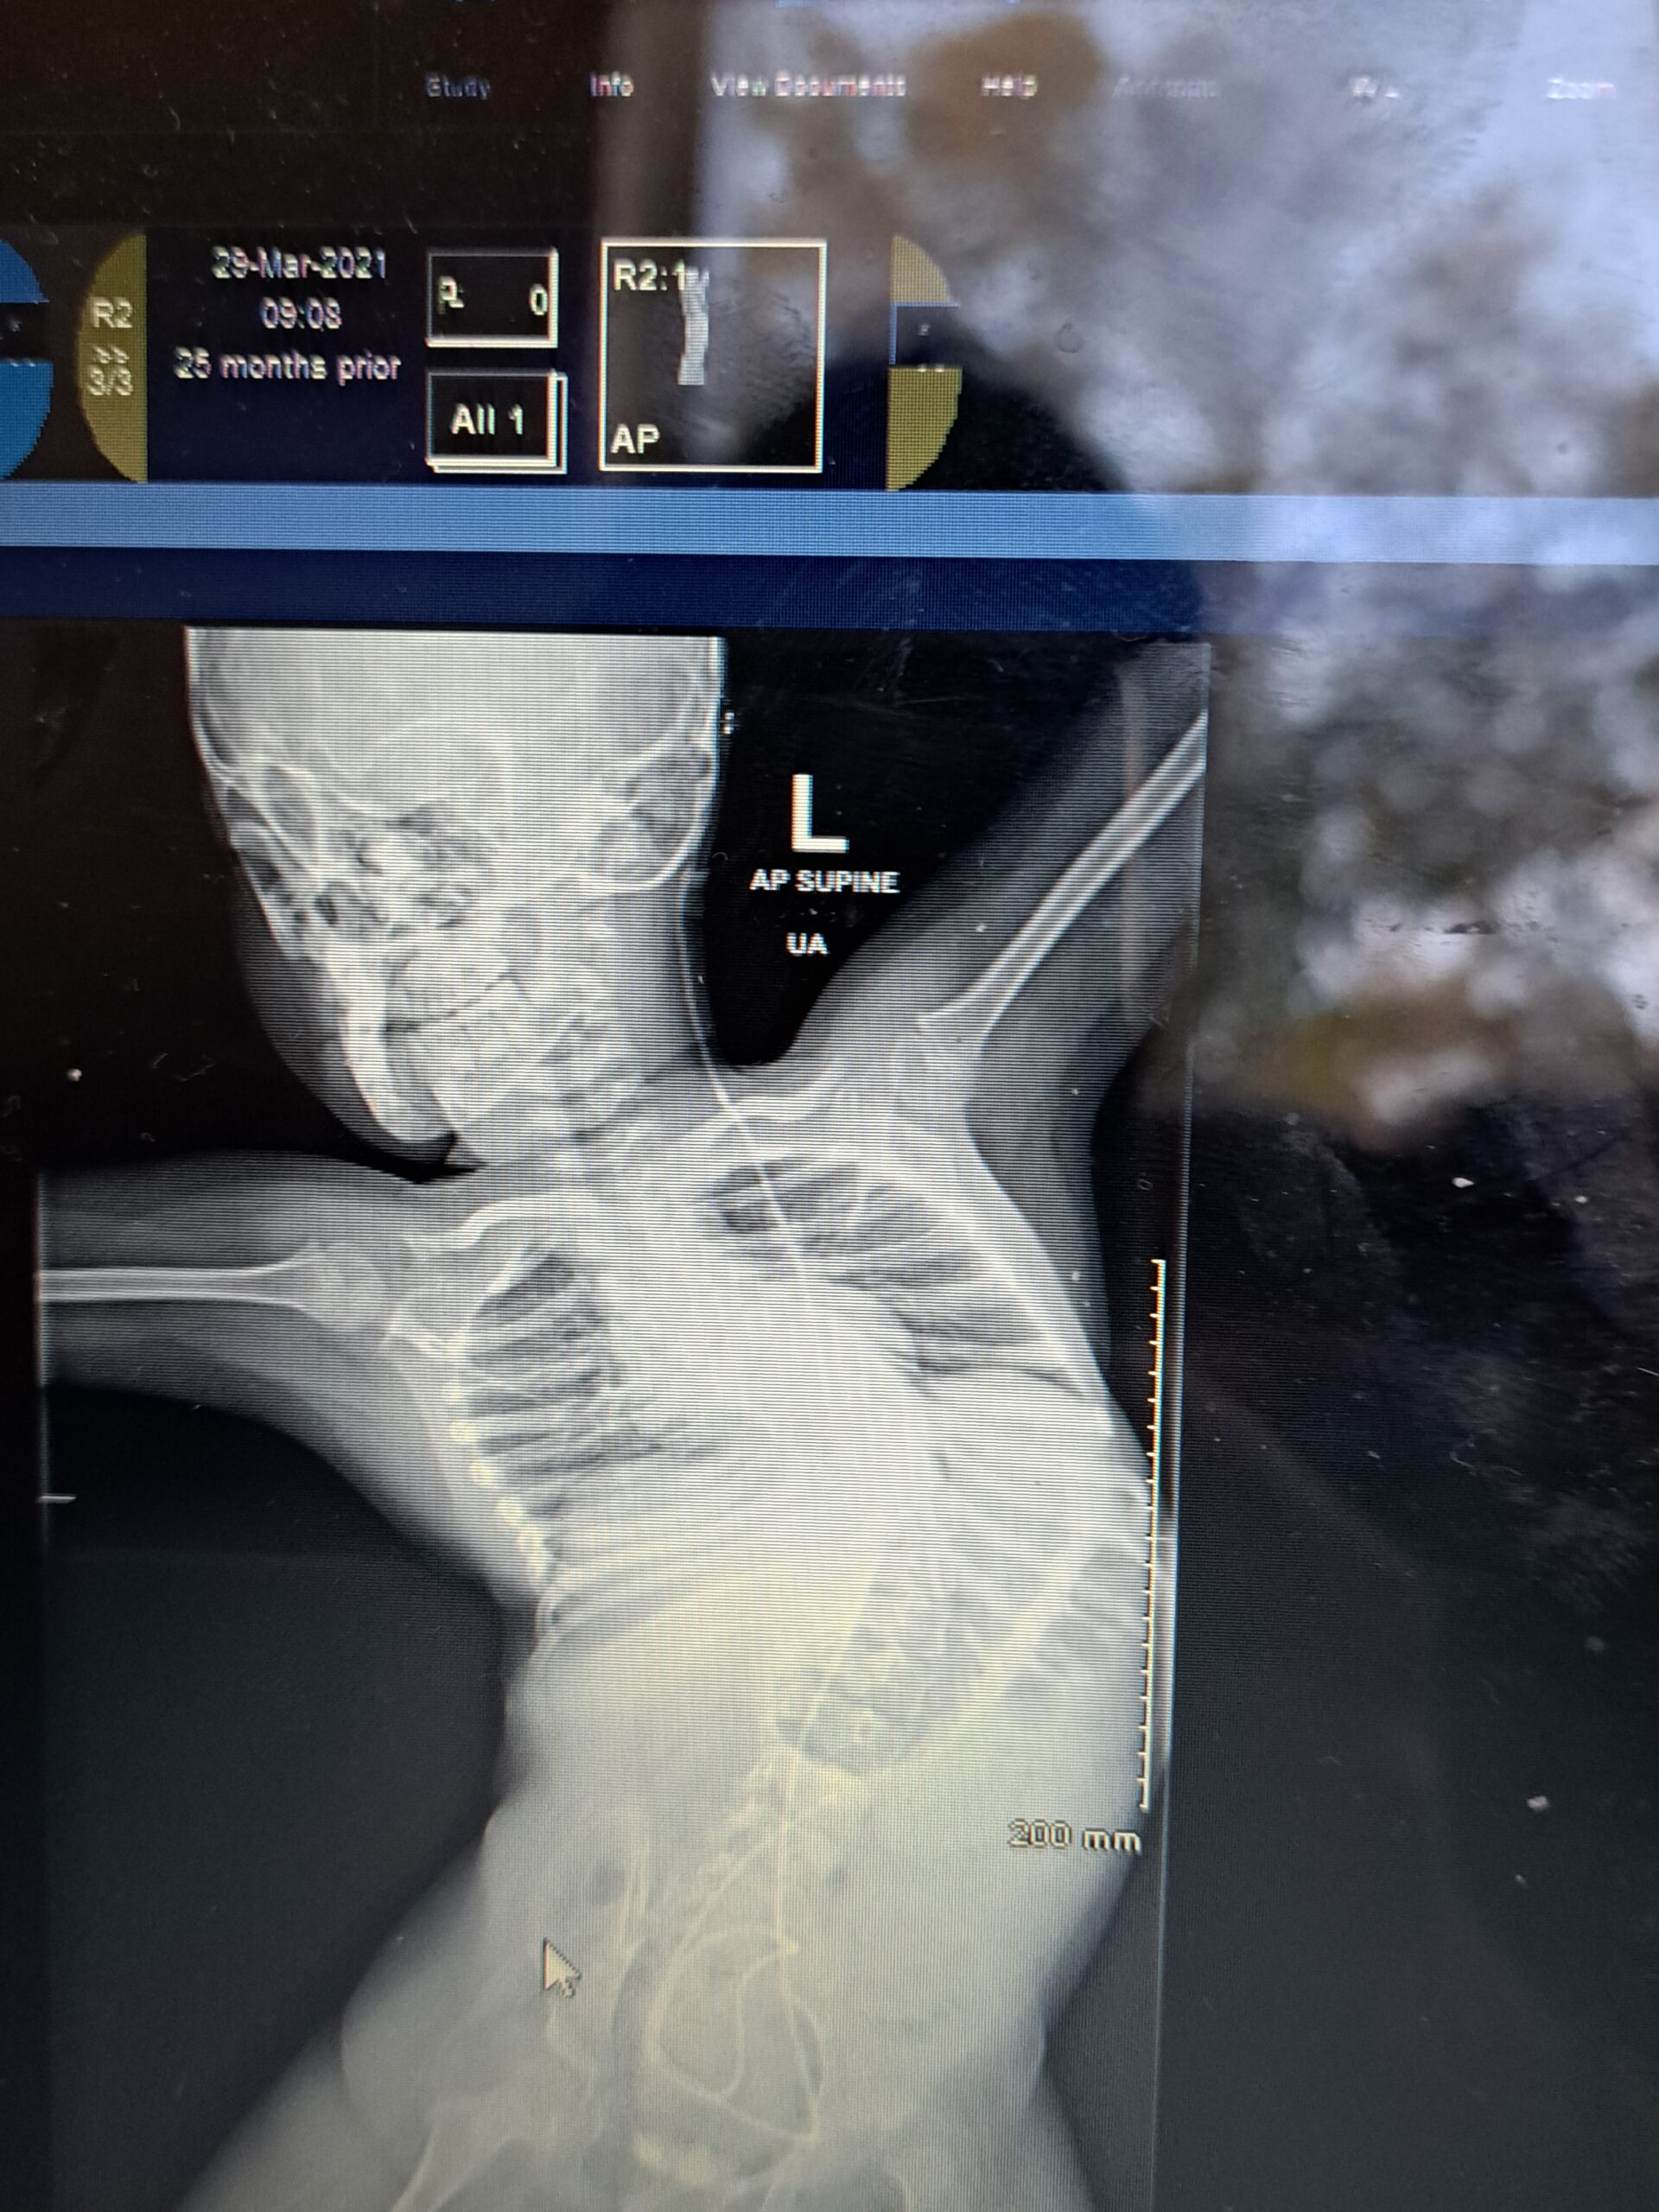

The curvature on Harvey’s spine is now somewhere beyond 80 degrees, meaning he is at risk of death unless he receives a surgical intervention. “He will die. He absolutely needs the surgery,” Morrison said.

The “cob-angle” – the measurement of a curve on his son’s spine should not be left go beyond 25 degrees, “by international standards”, and if the curve goes above that, “you get severe complications.”

While Harvey has waited for years for surgery his condition has worsened and is quite literally squeezing the life out of himself frail body. “Harvey now has got early onset chest-wall-disease, so his rib cage is currently crushing one of his lungs,” Mr Morrison said.

“From the scans we have it (the curve) looks like it is pushing on his heart, so all of his internal organs at the moment are completely shifting over to one side,” he goes on. The worsening of the curve on Harvey’s spine means “he can no longer sit in his wheelchair anymore”.

Harvey is “regularly admitted” to Temple Street, he has twice been blue-lighted to ICU, and has been admitted to the hospital in “respiratory distress” four times in as many months. Mr Morrison said the threat to his son’s life is “blatantly obvious” from his son’s scans, which show his twisted spine, to his son’s laboured breathing which he has videoed for doctors.